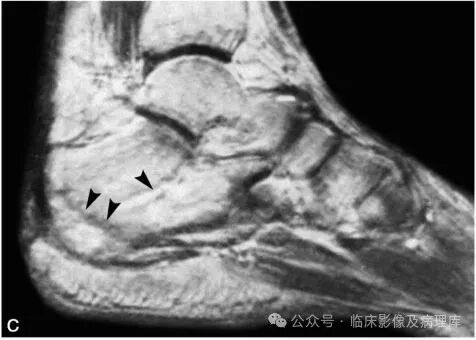

A、B.左侧胫骨正位片及CT冠状位重组像:左侧胫骨干骺端内侧骨松质区见片状骨质硬化改变,内缘皮质似不连续;C、D.左侧胫骨SE T1WI和脂肪抑制FSE T2WI:左侧胫骨干骺端内侧骨松质区见横行弯曲线样长T1信号,T2WI显示不清,周围示大片状长T1长T2水肿样信号